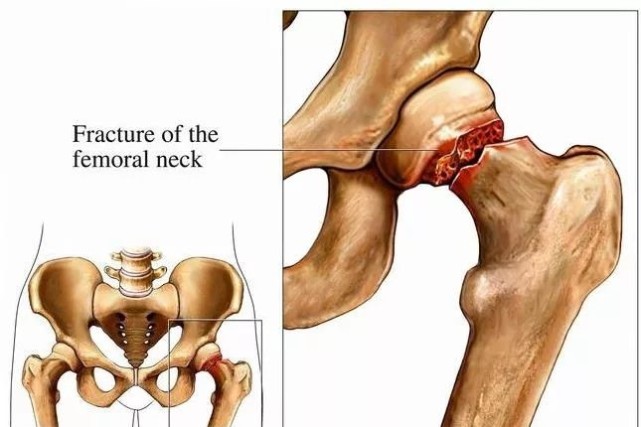

一、什么是髋部骨折?

髋部具体是我们身体的什么部位呢?其实就是我们通常所说的胯部,也就是大腿和臀部连接的部位。而髋关节就是连接大腿与躯干的重要关节,它的一边是大腿骨(也称作股骨),另一边是骨盆。髋关节由股骨头和髋臼所组成,它其实承受着人体上半部分所有的重量,它出现问题,直接影响人的人站立和走路。年轻的时候,摔一跤没啥事,很少出现骨折的,但是上了年纪,保护骨骼的肌肉渐渐萎缩,骨质也变得疏松了,尤其是绝经后的女性,骨量流失非常迅速,所以摔倒后很容易出现骨折。

而一旦髋部出现骨折,患者大多不能走路了,只能长期卧床,这对于患者来说不只是身体上,精神上也是非常沉重的打击。